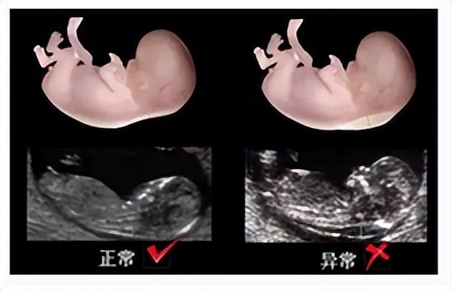

孕11-13周胎儿超声检查项目:NT(颈项透明层厚度)、鼻骨、心率、对双胎妊娠绒毛膜性判定等。

NT值是筛查21-三体综合征(唐氏综合征)等染色体畸形的一个较为敏感指标,此次超声检查可查出一些早孕期严重结构畸形。